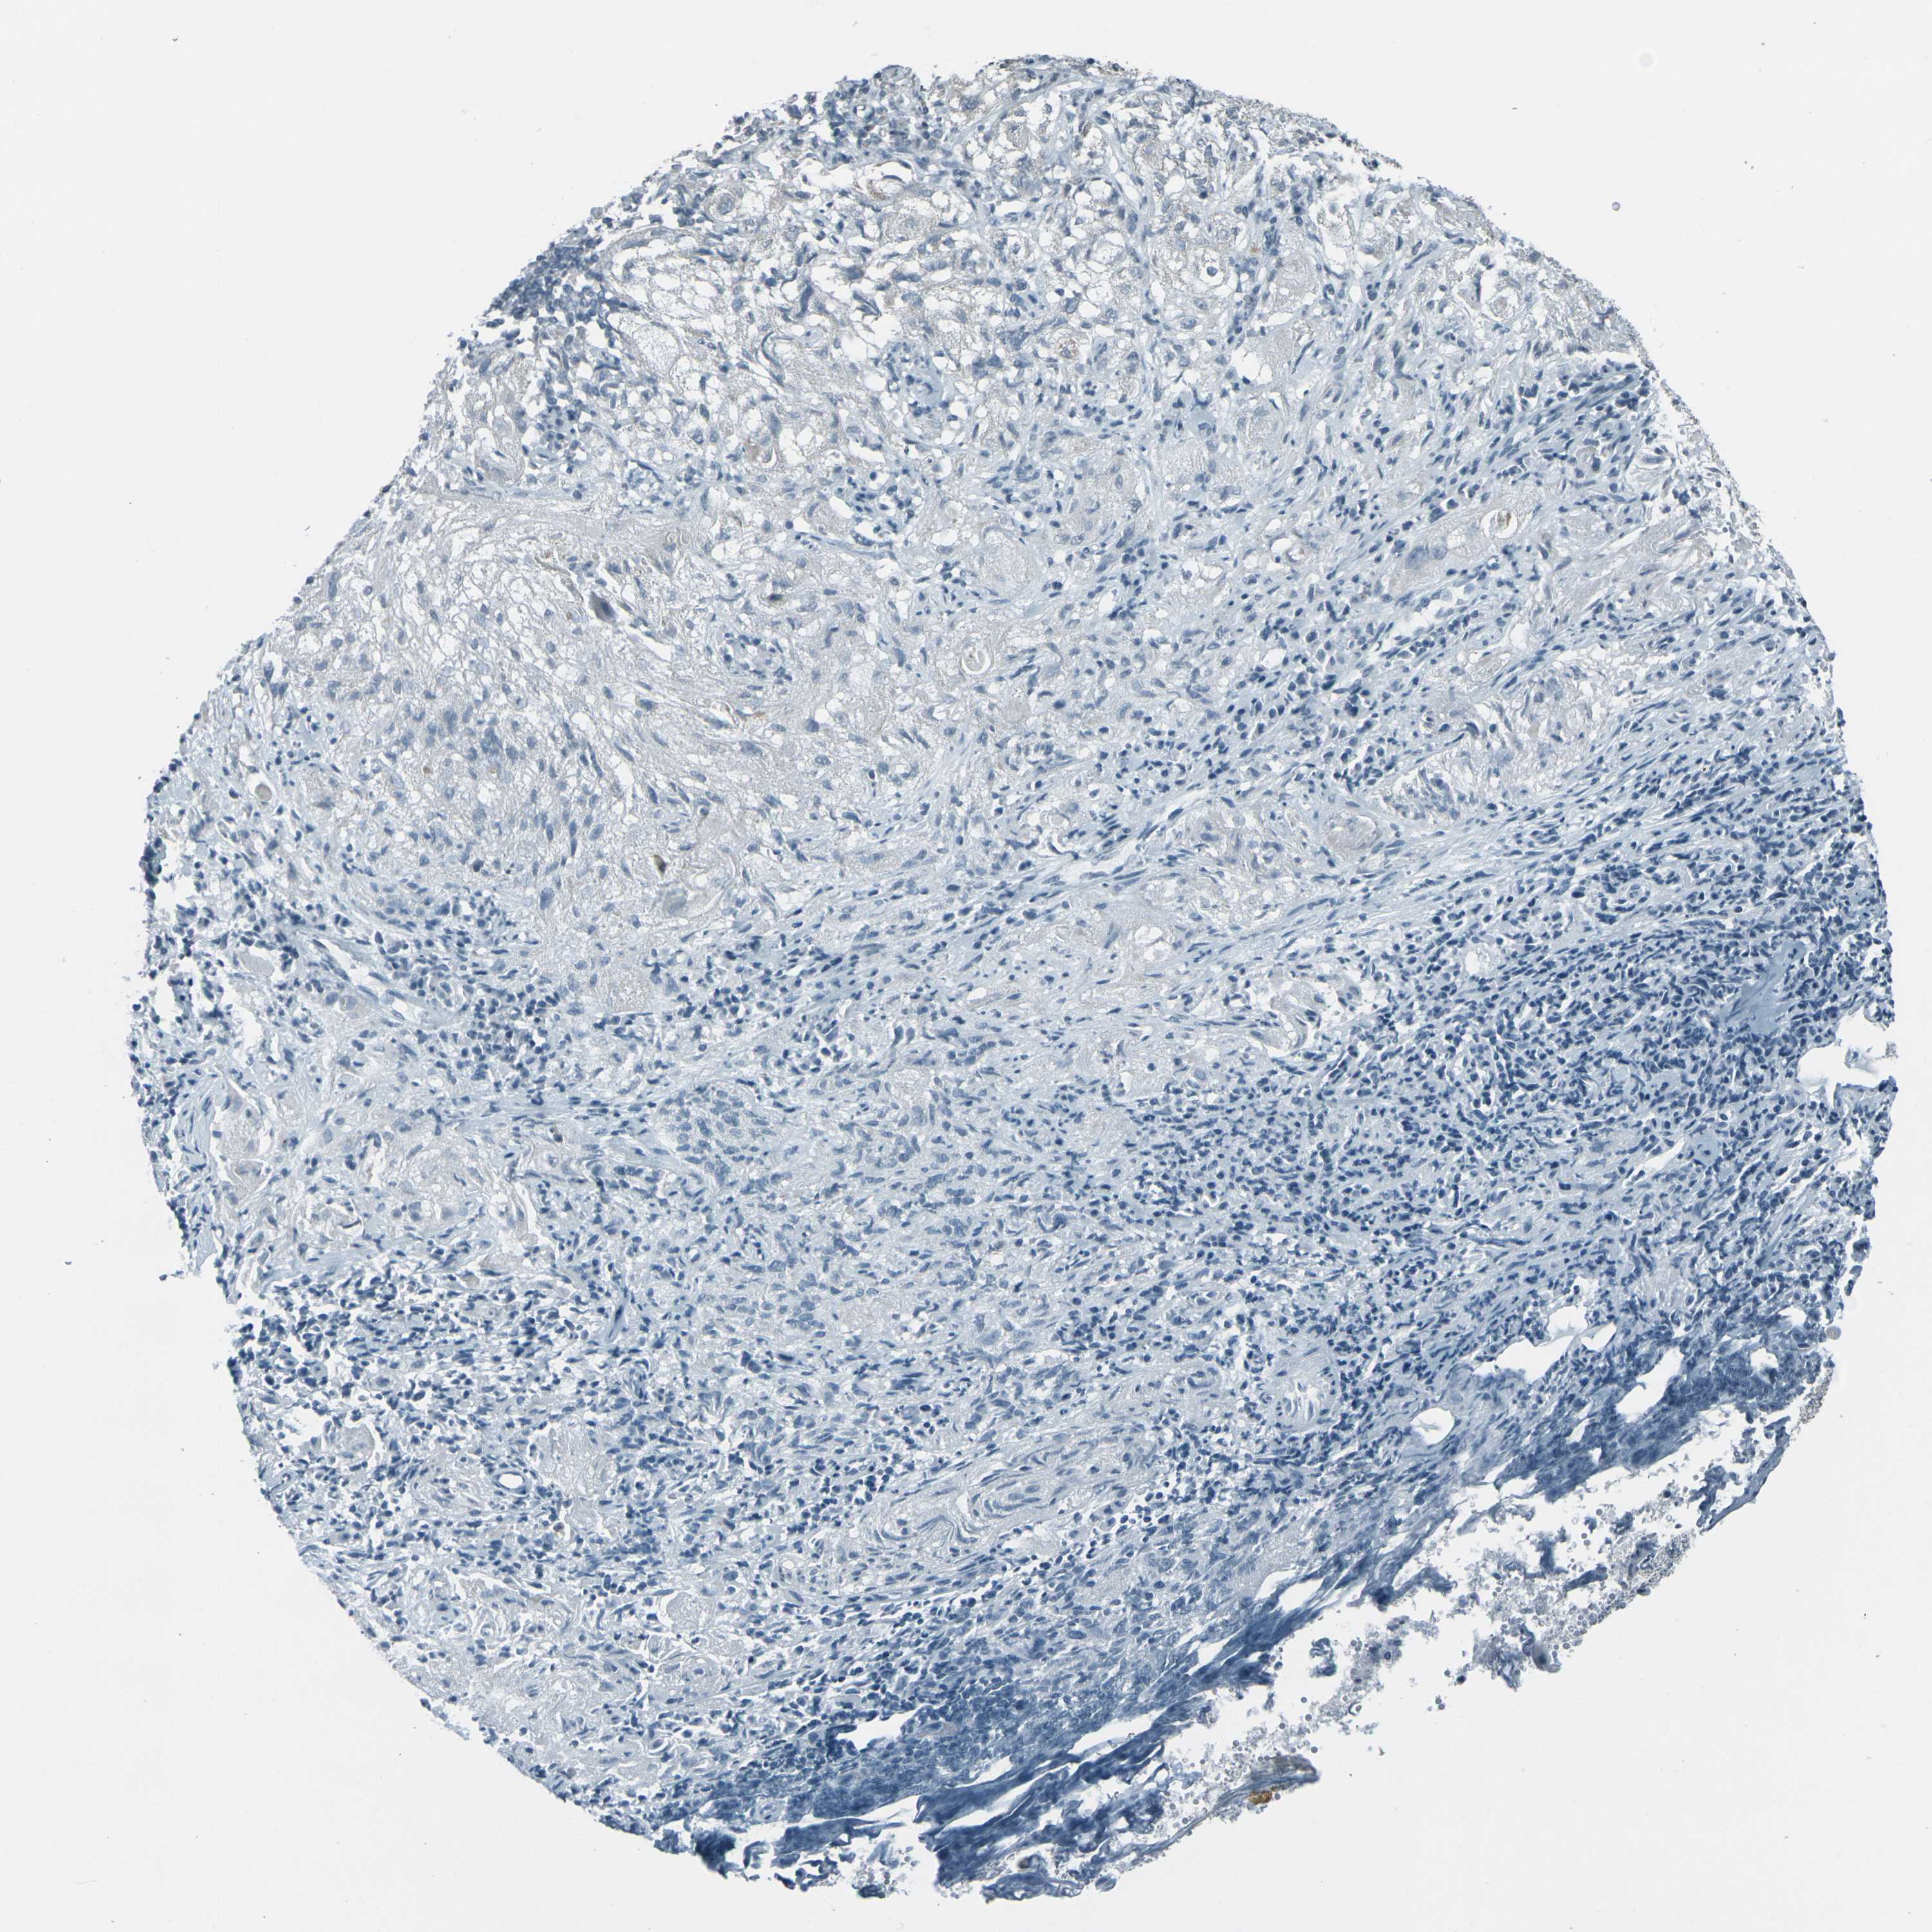

CANCER LUNG CANCER Show tissue menu

Lung cancer

Human cancer